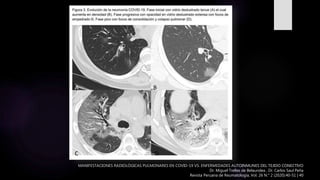

MANIFESTACIONES RADIOLÓGICAS PULMONARES EN COVID-19 VS. ENFERMEDADES AUTOINMUNES DEL TEJIDO CONECTIVO

Dr. Miguel Trelles de Belaundea , Dr. Carlos Saul Peña

Revista Peruana de Reumatología, Vol. 26 N.° 2 (2020):40-51 | 40

El COVID-19 típicamente induce una neumonía bilateral

difusa intersticial con lesiones en distribución asimétrica y

parcheada que afecta principalmente a la periferia pulmonar.